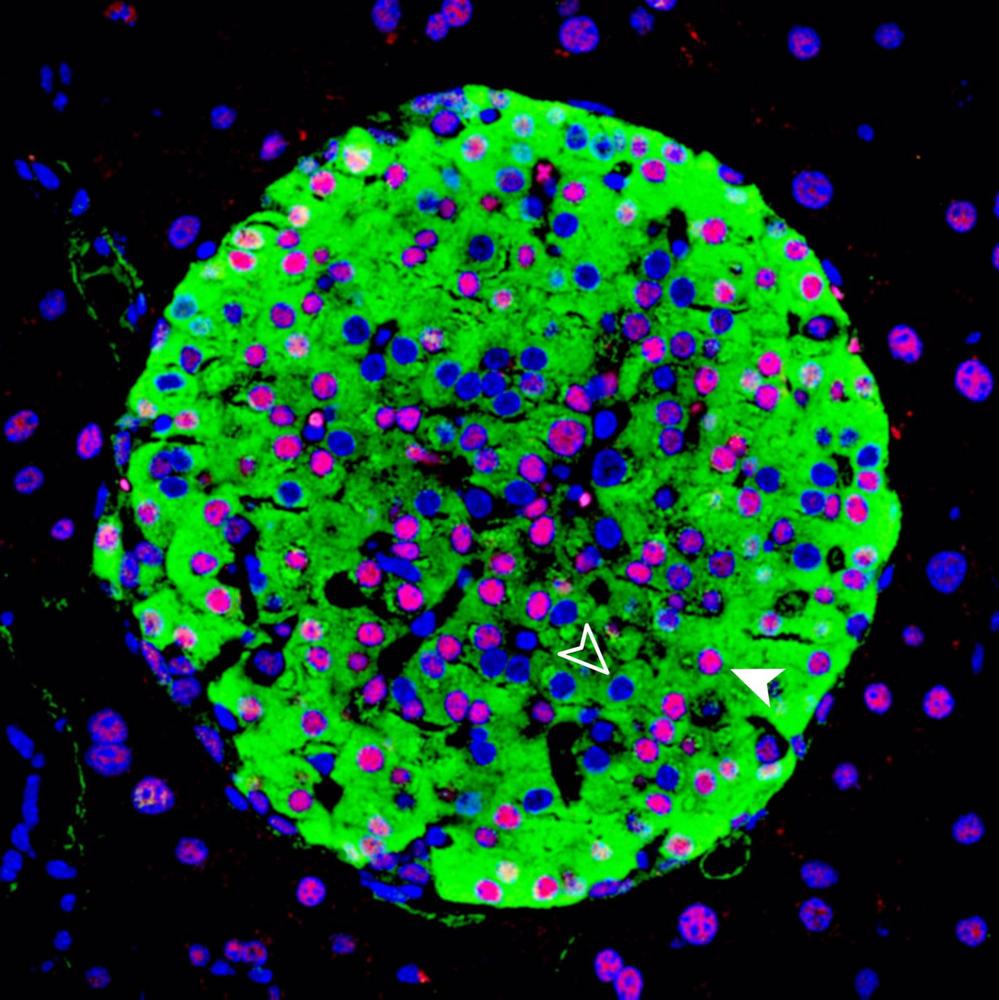

HNF1A es un gen que proporciona las instrucciones para producir una proteína llamada factor nuclear 1 alpha de hepatocitos. La proteína se expresa en muchos tejidos, y es particularmente importante para el páncreas, donde desempeña un papel en el desarrollo de las células beta. Las células beta producen la hormona insulina, que regula los niveles de azúcar en la sangre.

Las mutaciones en HNF1A hacen que las células construyan una proteína que no funciona como debería y que perjudica la función de las células beta. Esto hace que las personas desarrollen una enfermedad conocida como diabetes del adulto de inicio juvenil, donde los síntomas como el alto nivel de azúcar en la sangre pueden aparecer antes de que las personas alcancen la edad de 30 años.

Usando una combinación de modelos de ratón y de humanos, el estudio se centra en una parte enigmática del genoma cercana a la ubicación del HNF1A. Descubrieron que esta región, también conocida como un elemento regulador del ADN, tiene una función única que no se ha descrito antes: funciona como un reóstato. Si el gen HNF1A transcribe demasiado, HASTER lo controla y rebaja su actividad, si el gen está aflojando, HASTER ajusta la intensidad y aumenta su expresión.

El estudio demuestra que las mutaciones en HASTER causan la diabetes en ratones. «Esto es importante, porque demuestra que este tipo de elemento es crítico. Las consecuencias de eliminar HASTER son comparables a eliminar HNF1A en sí. HASTER podría ser una manera útil de manipular HNF1A terapéuticamente», ha destacado el doctor Ferrer.